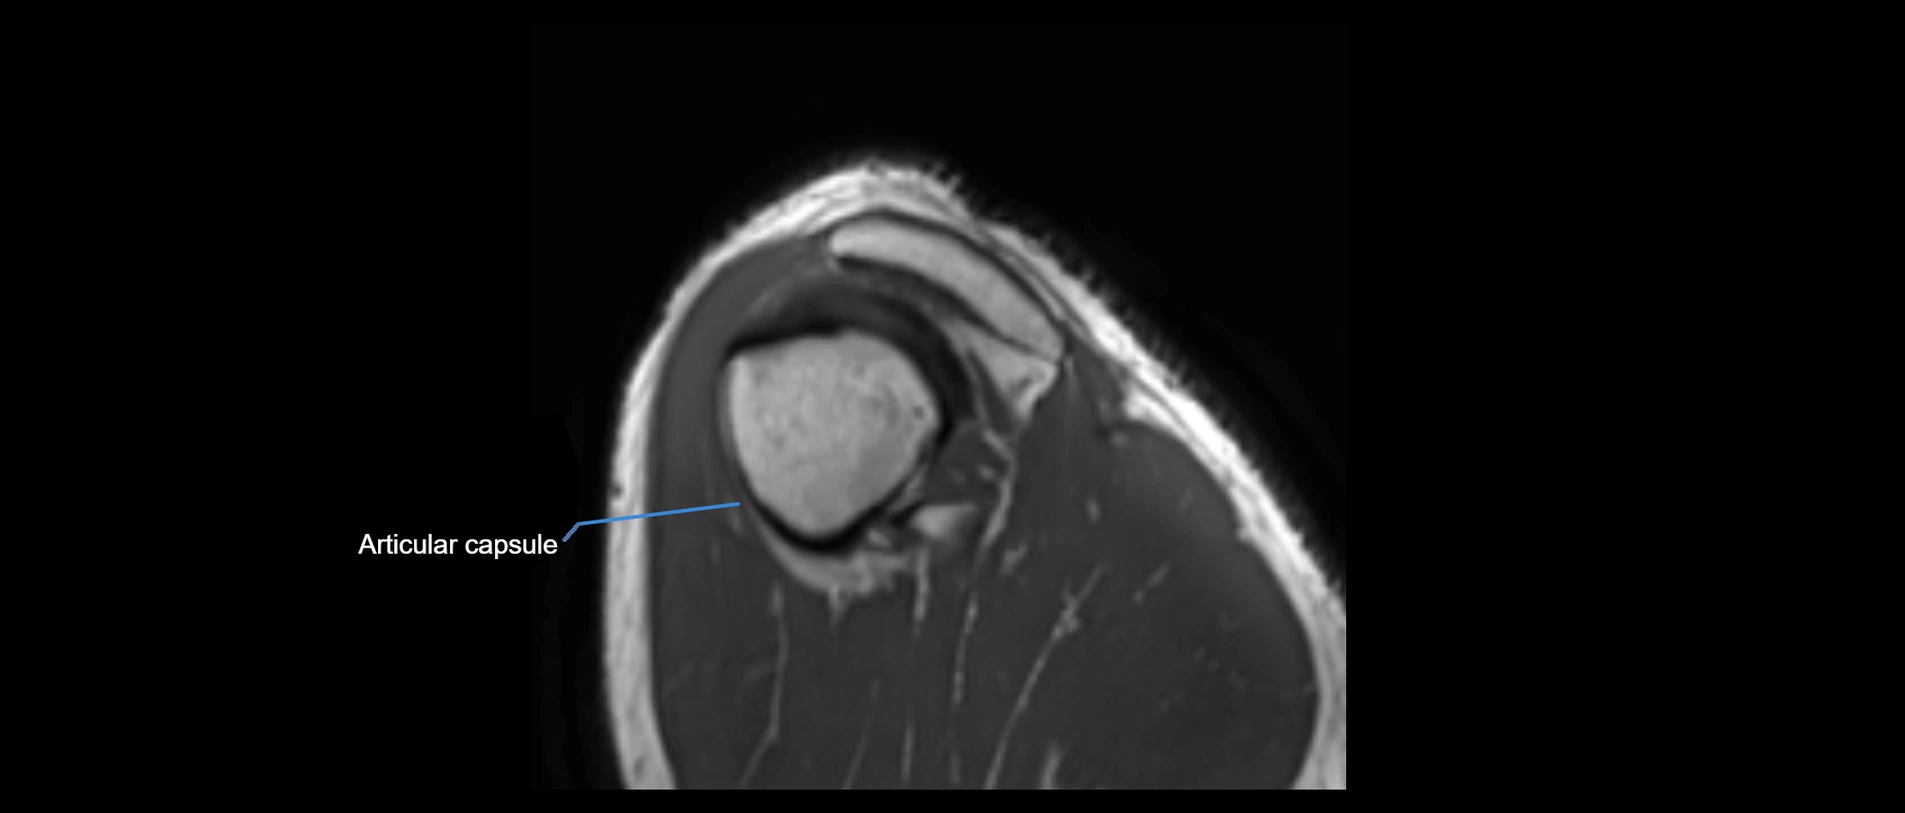

MRI images

image